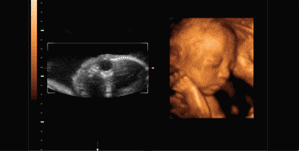

自打怀孕以后,小丽两口子就无数次猜想过宝宝的长相,听说四维彩超可以看到宝宝的样子,孕22周时,夫妻两人就迫不及待地来到医院做了四维,但做完检查的两人却大吵了一架,这到底是怎么回事?

小丽的这件事引起了网友的热议,很多人批评小丽的老公不懂事,小孩的长相本来就变化得很快,健康才是最重要的,而且四维是一定要做的,除了能提前和宝宝见面,更为重要的是,四维彩超能够多方位、多角度地观察宫内胎儿的生长发育情况,为早期诊断胎儿先天性体表畸形和先天性心脏疾病提供准确的科学依据。也有网友晒出了自己宝宝做四维时的动态图,萌萌哒的小家伙不知多可爱。

很多首次当父母的人看到四维照片后可能会觉得有点奇怪,宝宝怎么看起来黑乎乎的,甚至有点像外星人,这是因为宝宝长期在肚子里被羊水浸泡着,且四维照片是利用超声技术拍出来的,还隔着一层肚皮,肯定不能和平时相机拍的照片相比,宝宝出生后长开了会越来越好看的,况且做四维彩超并不是单纯地给宝宝拍几张照那么简单,更重要的是全面地检查宝宝各方面的发育情况。

二维彩超为平面影像,三维彩超为立体静态影像,四维彩超为立体动态影像。四维彩超相比二维和三维彩超,清晰度和精准度更高。四维彩超排畸率较高。而且四维彩超可以将宝宝的动态刻录下来,方便父母观看。医生指出,四维彩超的最佳检查时间为孕22-28周,这段时期检查,胎儿活动度大,体表也比较丰满,有利于胎儿四维超声成像和胎儿畸形筛查,是排畸的最好时期。